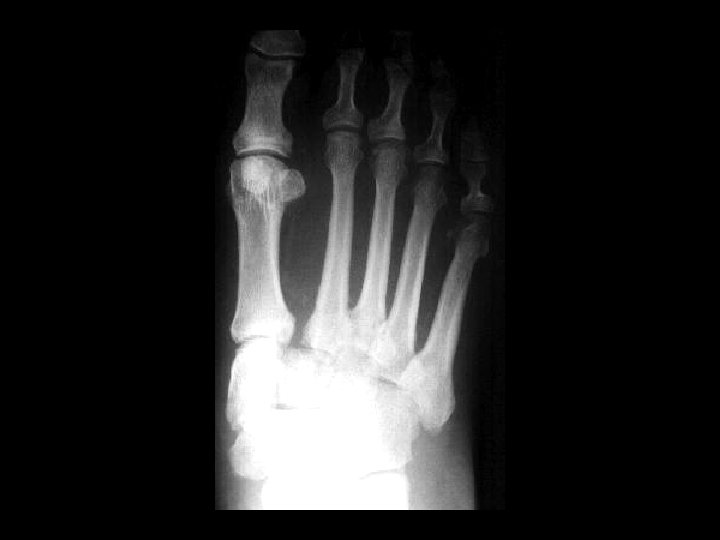

Septic Arthritis • Findings: – Lytic and sclerotic destruction of the great toe MTP joint – Joint space narrowing – Periosteal reaction – Soft tissue swelling • ddx: – Charcot joint – Metastasis with pathologic fractures